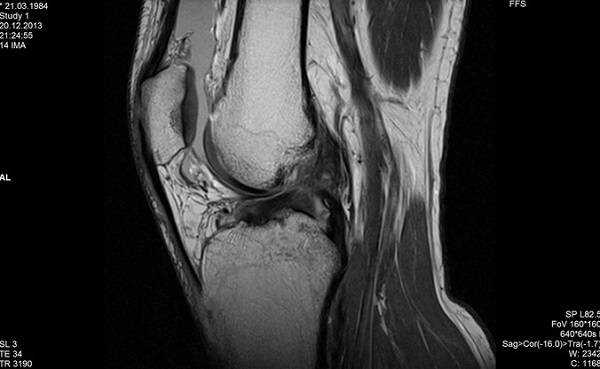

Остеосаркома коленного сустава на МРТ